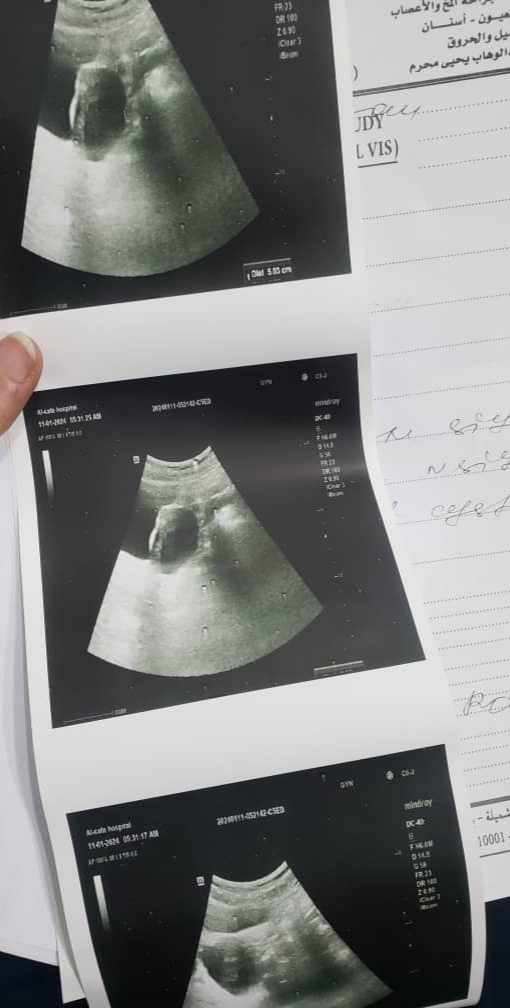

لدي تكييس في المبيض واريد تشخيص الحاله

هل التكيس على المبايض خطير وما مدى خطورته؟ وهل علاجه يسير؟